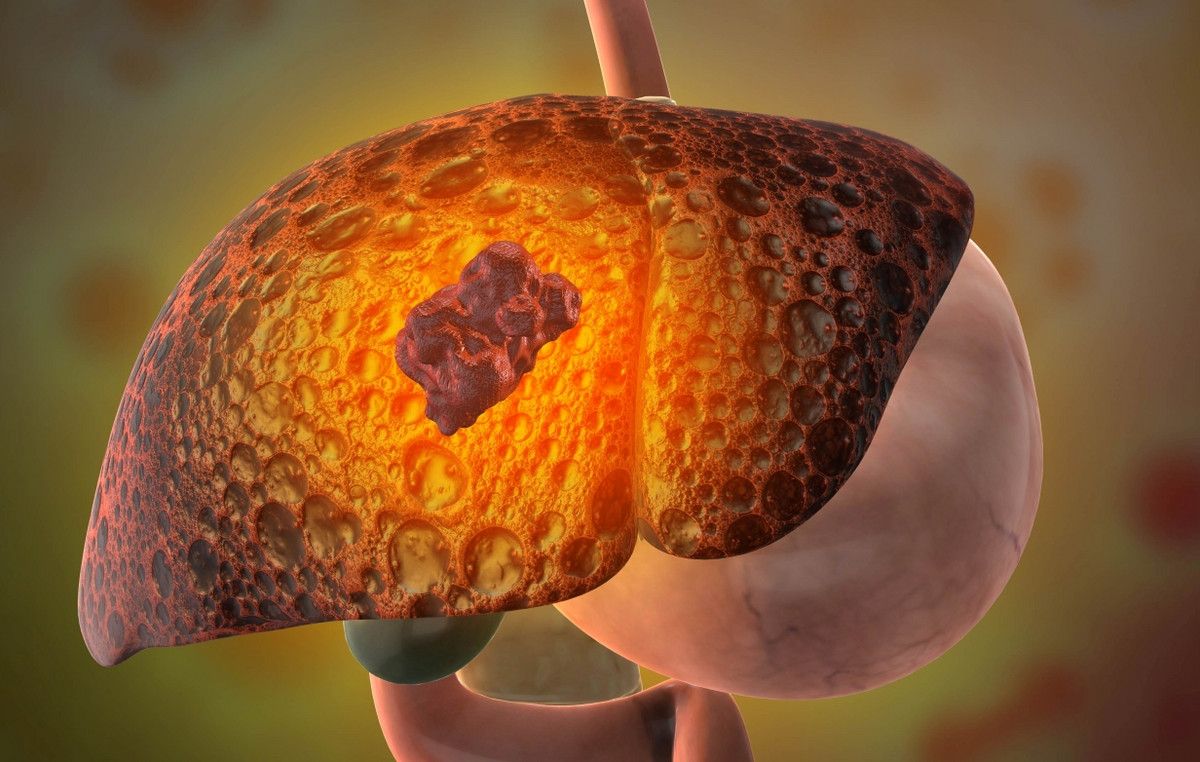

Si vous avez souvent : des Fatigues , ventre gonflé ,urines jaunes et les yeux jaunes C'est le signal d'alarme de votre Foie qui est silencieusement en danger , rempli des graisses et des toxines qui vous fatiguent.

⛔Pendant que vous attendez, le corps souffre en secret : ❌Hépatite A, B , C, D ❌Foie gras ❌Ballonnement La fatigue devient chronique. La peur de la « grande maladie » s'installe.

Soutien Hépatique : Renforce les fonctions du foie pour une meilleure santé globale. Adieu Foie Gras : Il brûle l'excès de graisse qui étouffe votre foie et il le nettoie